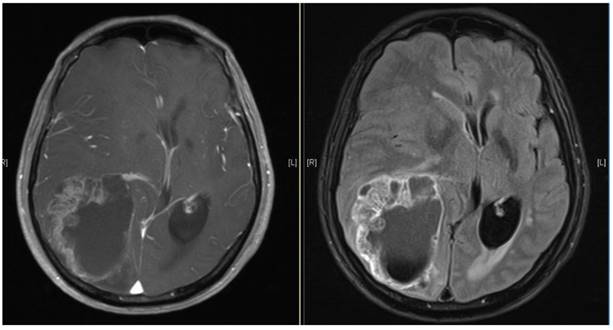

Get Brain Tumor Medicine Name PNG. The drug names link to nci's cancer drug information summaries. Brain tumor symptoms include headaches, nausea or vomiting, balance and walking problems, mood and personality changes, memory problems, and numbness or tingling in the legs.

The most common primary brain tumors a tumor that begins in the brain or adjacent tissue is called a primary brain tumor. Sometimes, people with a brain tumor do not have any of these changes. Primary brain tumors include any tumor that starts in the brain. Symptoms include headaches, nausea, and coordination problems.